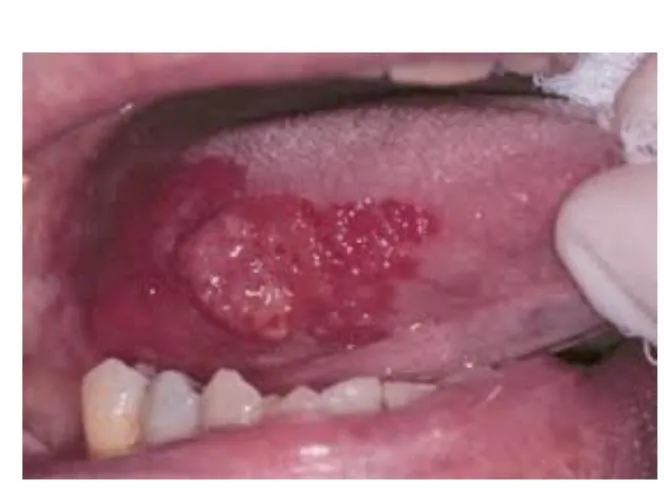

Oral Cavity Tumor

- Diagnosis: Oral cavity tumor (Erythroplasia).

- Possible Malignant Cells: Squamous cell carcinoma.

- Management: Observation, biopsy, surgical or laser excision.